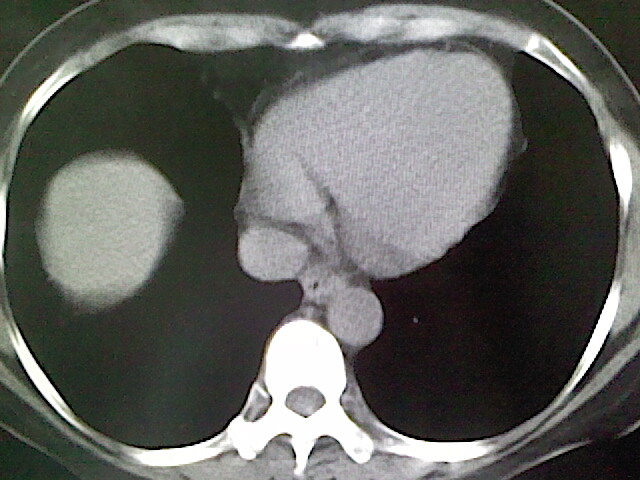

女,52岁,咳嗽,咳痰多日

左下肺陈旧纤维索条!

左肺舌段炎性改变

我见过几例,为炎症后纤维条索

慢性炎症后改变

考虑慢性炎性病灶粘连牵拉改变。

左肺舌叶纤维锁条病变。

左肺上叶下舌段炎症并局部胸膜反应。

左肺舌叶纤维索条影。

左肺舌叶段陈旧性病变

左肺舌段炎性反应。片子的质量太不好了。

左肺舌段炎性

炎性改变

左肺舌叶纤维索条影